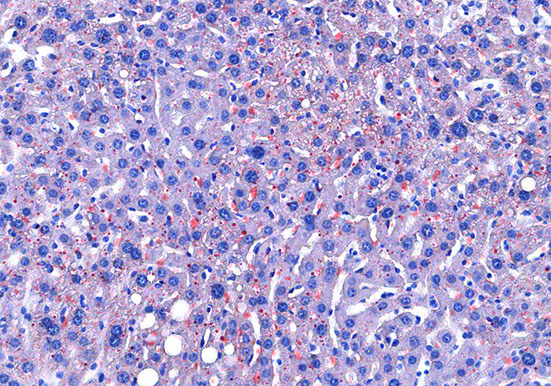

实验结果展示:

<

油红O-肝>

油红O对脂滴的染色机制一般认为是物理学上的溶液作用或吸附作用,借溶液作用使脂质染色,即油红O先溶于60%异丙醇中,然后切片浸入油红O染液中时,油红O在组织脂质的溶解度较60%异丙醇中的溶解度高,所以在染色时油红O从60%异丙醇中转移入脂质中使脂滴显示红色。